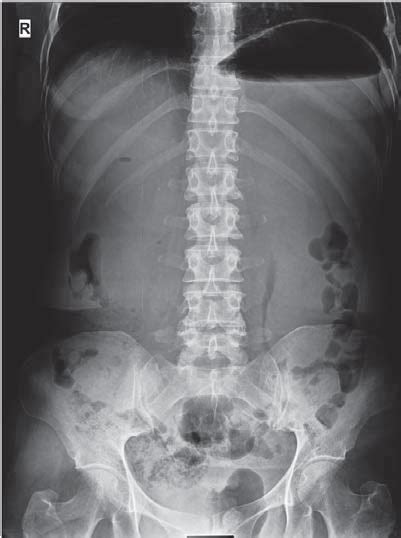

Las modificaciones verticales de la posición de los molares permanentes presentan mayores dificultades. Dichas modificaciones son necesarias cuando existe o se teme una apertura de mordida en presencia de un componente de crecimiento vertical. En este caso se hace necesaria la intrusión de los primeros molares, a fin de provocar un rebajamiento de la mordida o como mínimo prevenir una mayor elongación vertical. La dificultad aquí reside en la aplicación de fuerza, la cual habitualmente debe lograrse mediante un arco facial de tracción alta.

Fig. 2. Mediante intrusión de los molares puede rebajarse la mordida.